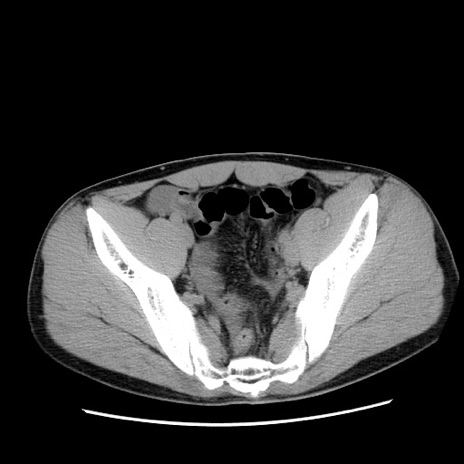

症例36(横断像)

【症例】20歳代 男性

【主訴】心窩部痛

【現病歴】今朝より上腹部痛あり。一旦軽快していたが再度出現したため救急要請。昨日夕に白身の魚を含む刺身を食べた。

【身体所見】BP 136/89mmHg、HR 74/min、BT 37.0℃、腹部:膨満、軟、心窩部に圧痛あり。反跳痛なし、筋性防御なし、腸雑音やや亢進あり。

【データ】WBC 17700、CRP 0.48